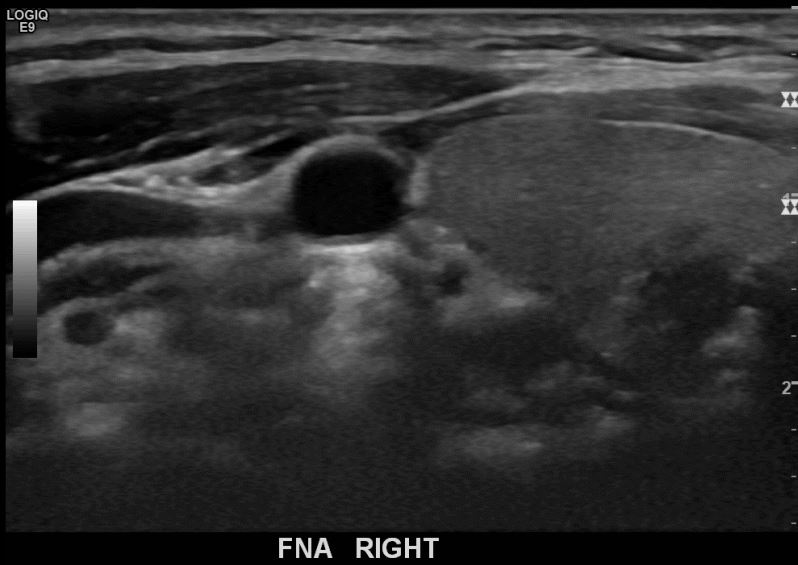

상기환자  40대 후반 여성분으로 의심스러운 우엽혹 세포검사진행후 갑상선암으로 진단되었습니다